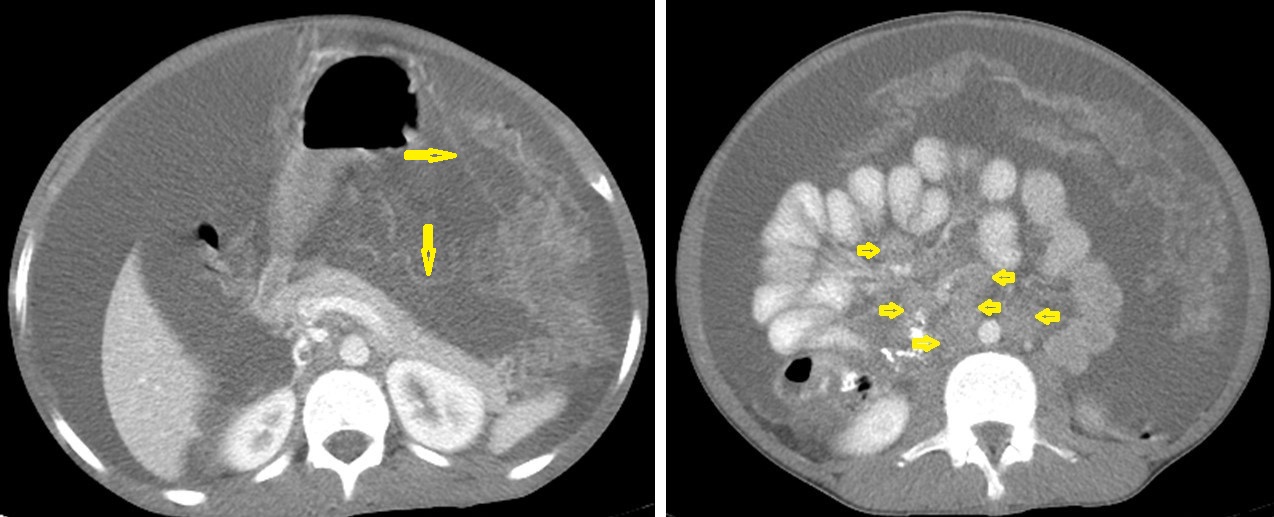

Figure 23. Renal TB in a 39-year-old man. Selected axial computed tomography images show (a) focal hyperdense non-enhancing nodules, with the largest at 26 mm, with calcified rim in the upper pole of the right kidney with focal scarring of the kidney. (b,c) Approximately, 20 mm cystic lesion in the upper calyx with focal calcification, most likely dilated calyx; and (d) 11 mm focal parenchymal calcification in the middle calyx.